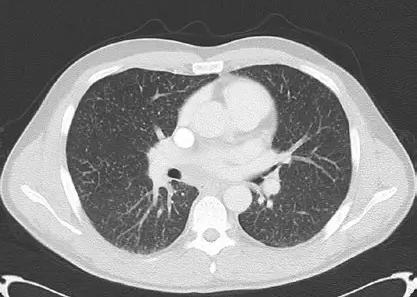

肺结核肺部ct表现(2)

肺结核1例ct影像讨论

继发性肺结核

48 两上肺空洞,斑块,条索,两肺支气管播散,树芽征---------提示肺结核